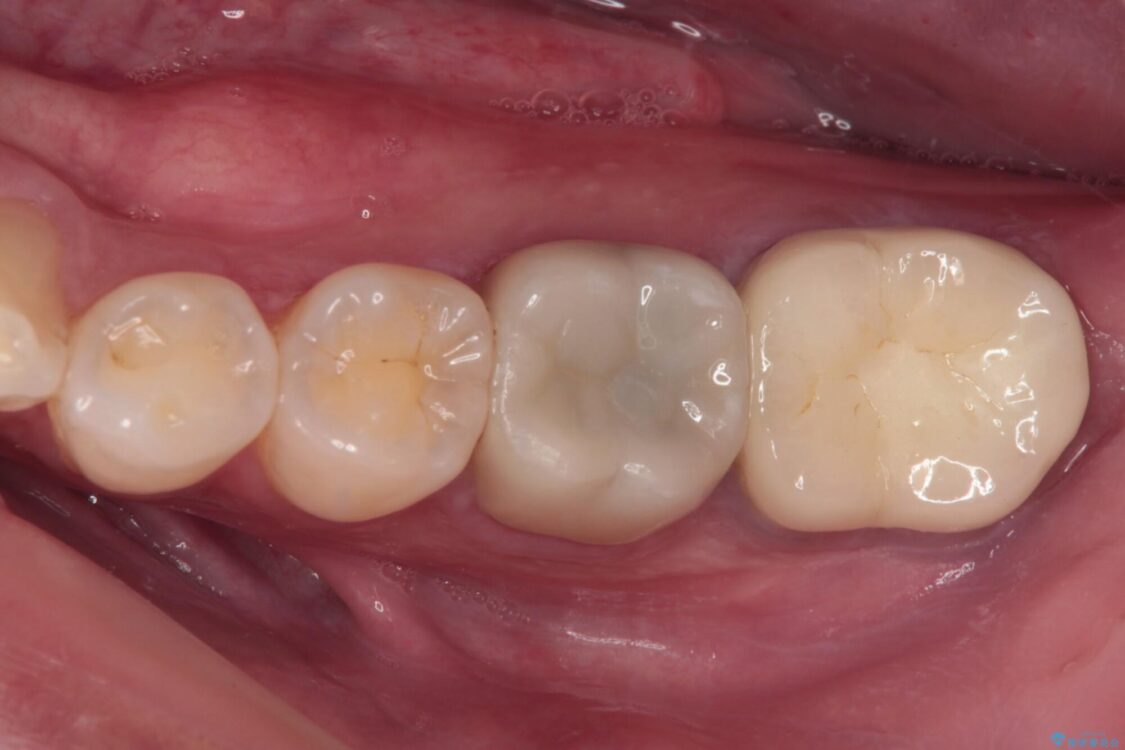

治療後

• 海外赴任前に治したい 割れてしまった奥歯のオールセラミッククラウン 治療後画像